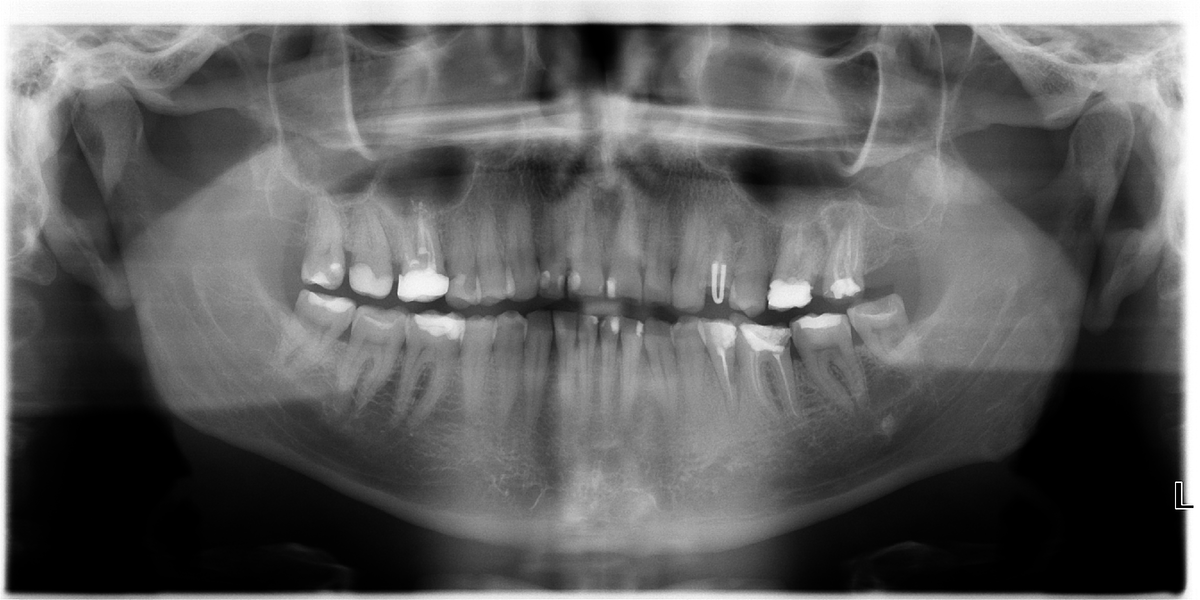

Панорамный снимок